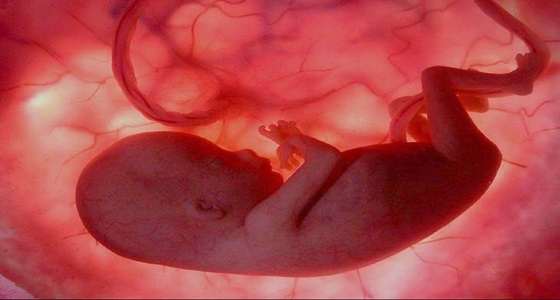

وفقا للقانون.. عقوبة صارمة لمن يحقن أجنة امرأة من غير زوجها